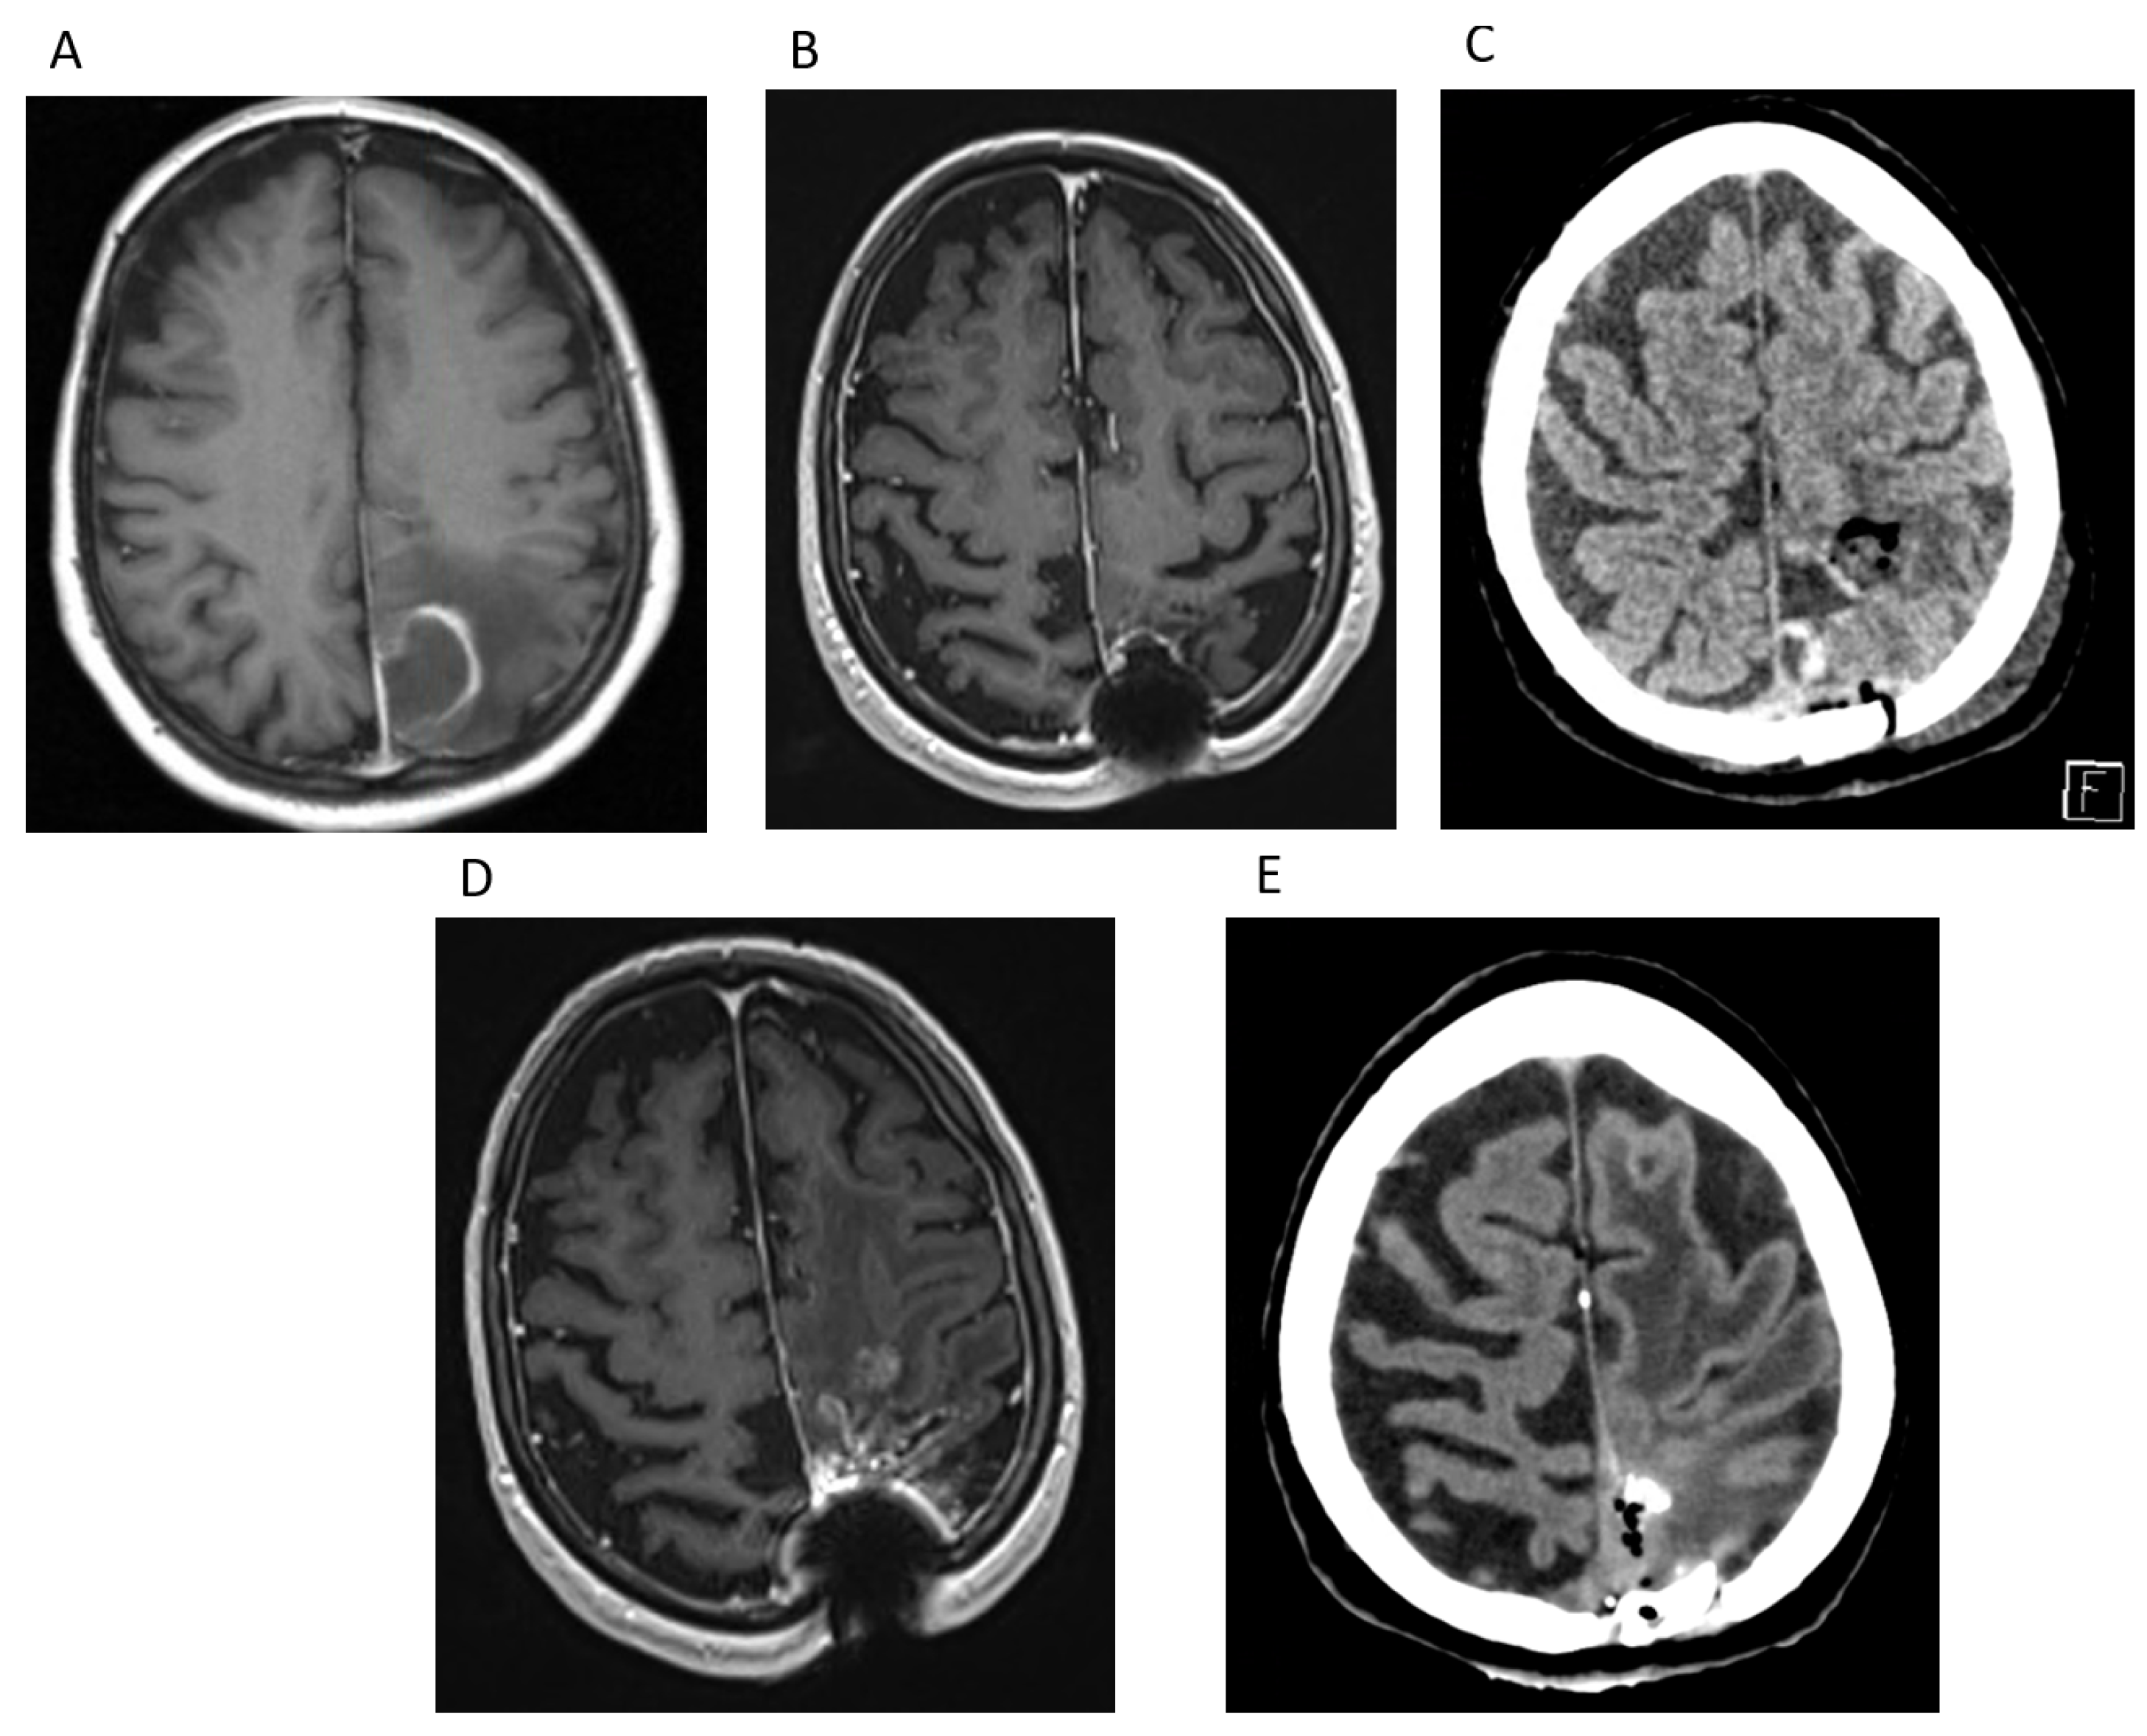

Case Report 1

Case Report 2

Case Report 3